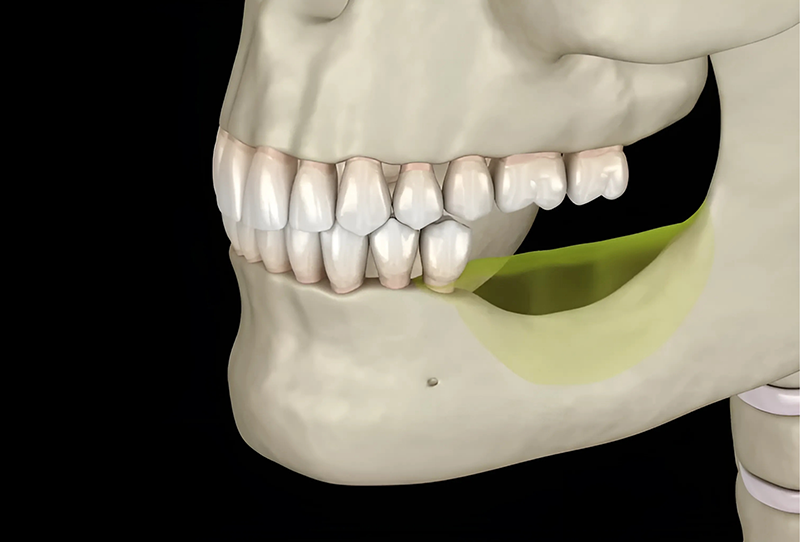

• Không đủ mật độ để đặt trụ Implant: Xương hàm bị tiêu biến sẽ không có đủ chiều cao, mật độ đặt trụ Implant, khi đó phải thực hiện ghép xương hoặc nâng xoang (áp dụng với xương hàm trên) để đặt trụ thuận lợi.

• Trụ Implant bị đào thải: Nếu không tiến hành ghép xương trước khi đặt trụ, xương hàm sẽ không đủ thể tích để trụ Implant được cố định chắc chắn, khi đó Implant dễ lung lay, dẫn đến bị đào thải.

Để có thể trồng một trụ Implant vững chắc, mật độ xương hàm cần đạt tiêu chuẩn tối thiểu từ 8 - 10mm về chiều cao hoặc độ dày, tùy theo vị trí cấy ghép. Vì vậy, bác sĩ cần đánh giá chính xác mức độ tiêu xương hàm của từng cá nhân để lập phác đồ điều trị phù hợp. Tuy nhiên, trong một số trường hợp tiêu xương nhẹ, vẫn có thể thực hiện cấy ghép Implant với các giải pháp hỗ trợ, chi tiết sẽ được đề cập trong nội dung dưới đây.